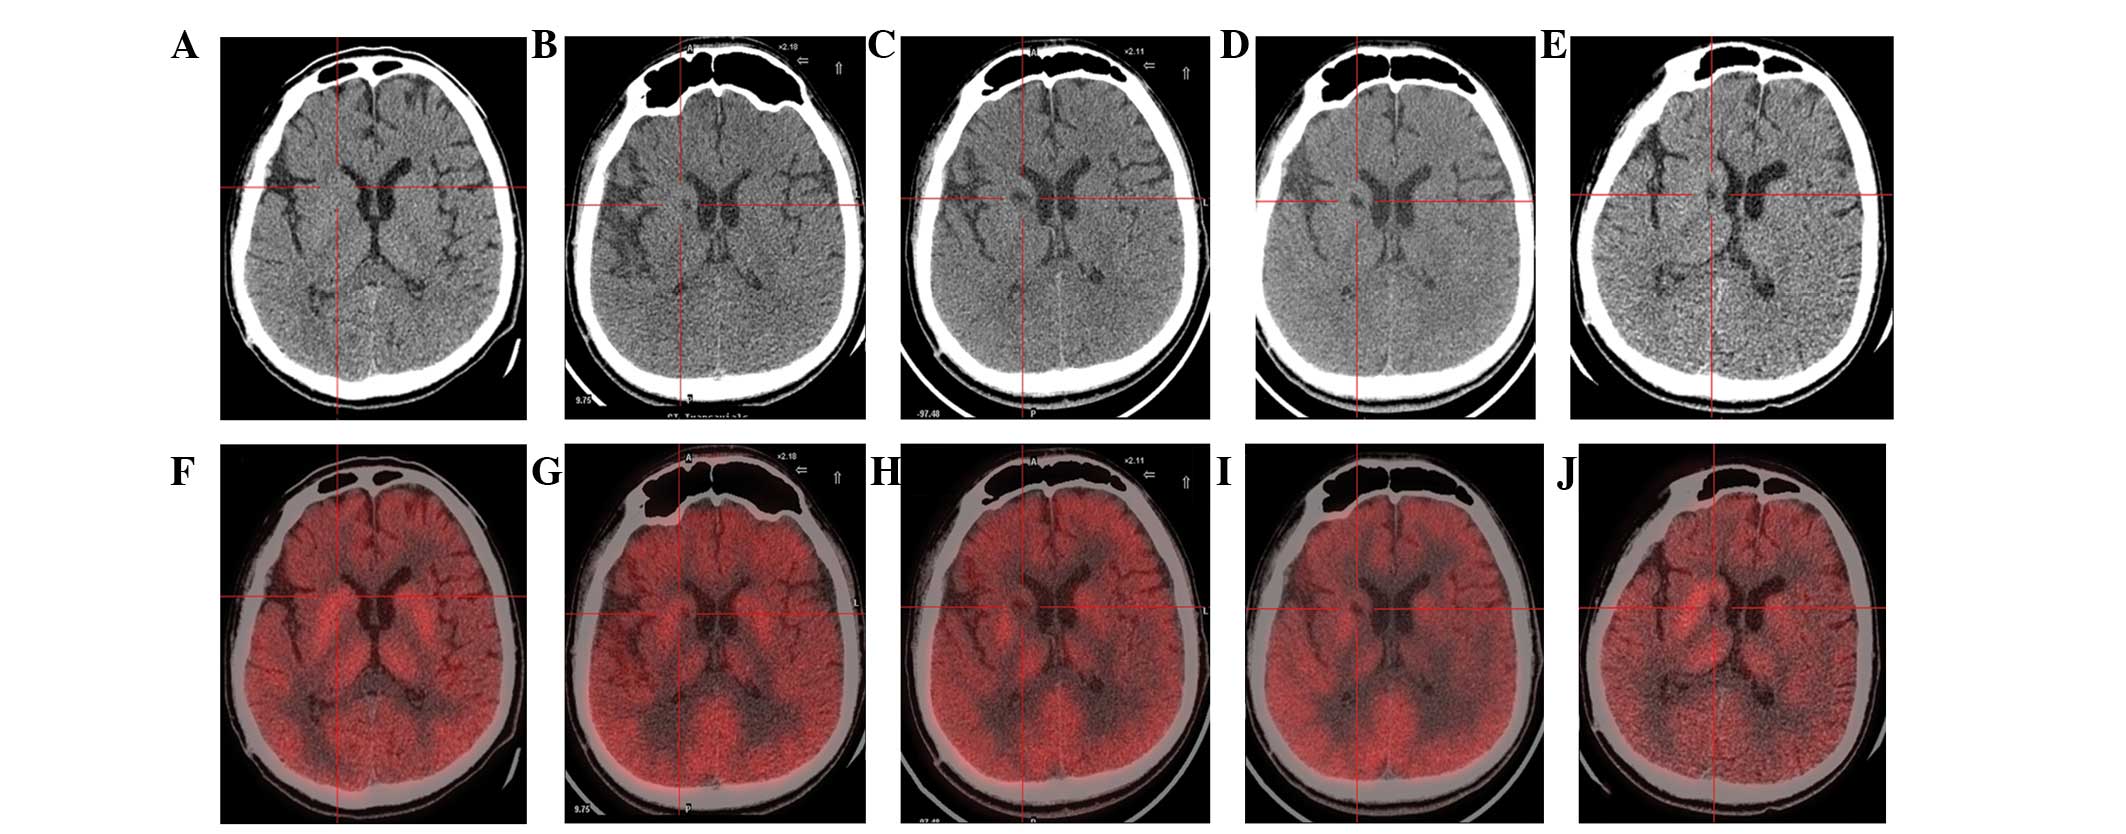

(A) 術前CT顯示腦萎縮。

(BE)術后1年、2年、3年、4年CT與術前相比均無明顯變化。

(F)術前18F-氟脫氧葡萄糖 (FDG) PET 掃描顯示,整個大腦皮層FDG攝取彌漫性減少,細胞核FDG攝取相對高于其他區(qū)域。術前1天,豆狀核和丘腦的標準化攝取值 (SUV) 平均值/最大值分別為4.3/5.8和3.3/4.5。

(GJ) 神經干細胞移植治療后分別 1、2、3 和 4 年的 18F-FDG PET 掃描顯示,雙側植入部位的豆狀核和丘腦對 18F-FDG的攝取增加(紅十字)與植入前相同部位進行比較。 豆狀核和丘腦的SUV*平均值/最大值在 1、2、分別是術后3年和4年。 該結果表明移植后葡萄糖代謝比移植前稍高。

CT(圖1b-e)和MRI(圖2b-d)掃描顯示4年隨訪期間沒有顯著變化。 手術前1天(圖1f)和手術后1、2、3和4年(圖1g-j) 獲得18F-FDGPET掃描。術后雙側植入部位豆狀核和丘腦18F-FDG攝取值較術前增加。這一結果表明,自移植以來,葡萄糖代謝逐年略有增加。